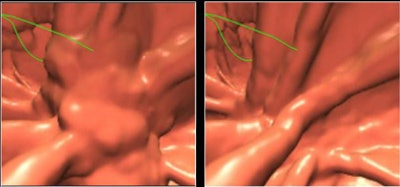

| Morphological enhancement is designed to determine which part of the tagged region should be preserved. Structures with rutlike shapes (submerged fold) and cuplike shapes (submerged polyp) are enhanced, while other structures are de-enhanced. Morphological enhancement uses local morphologic structure based on eigenvalue signatures of the 3D Hessian matrix (H) of a volume (I) (above). Submerged folds and polyps are enhanced by a combined Hessian enhancement function (below). |